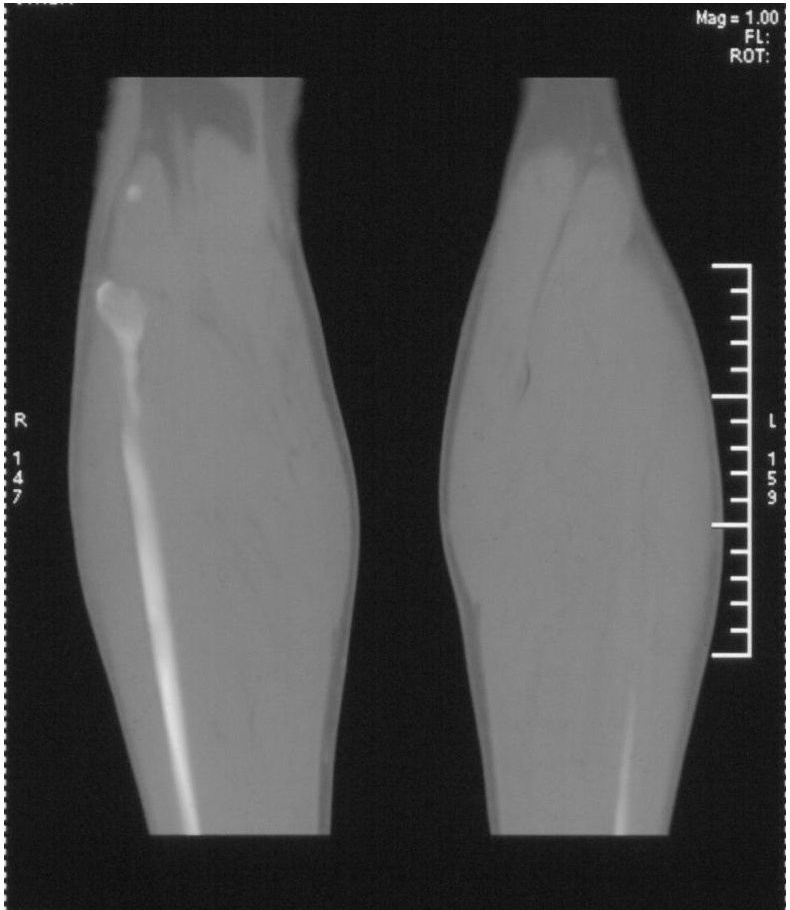

该患者到某三级医院进行会诊,并重新作了平片检查,认为畸形性行骨炎: